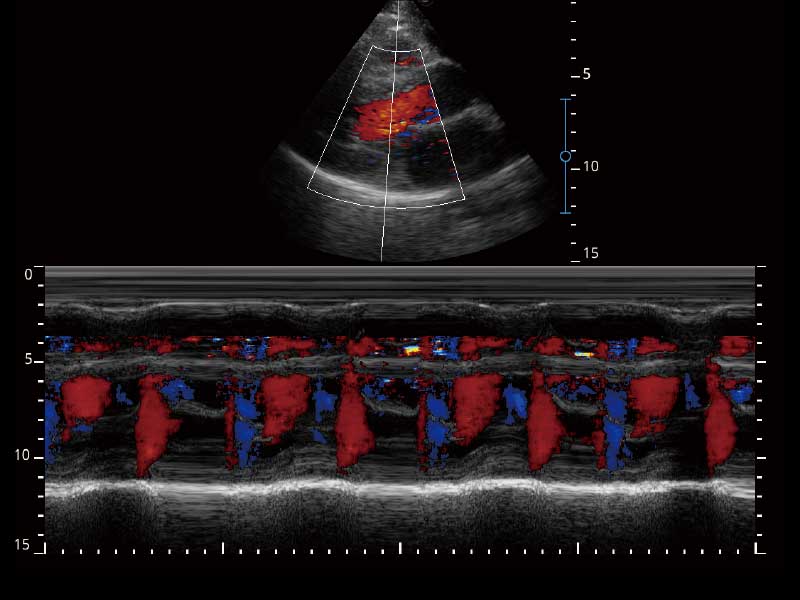

临床图